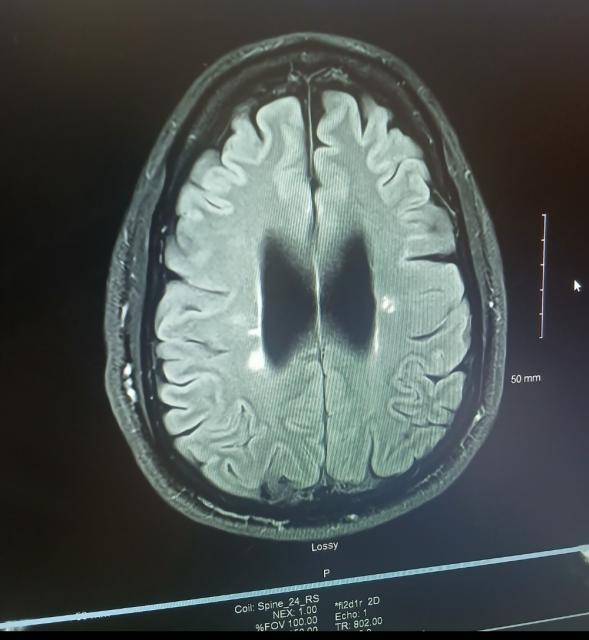

I had lime test done Maybe twice Its been a few years. MRI's show classic MS confirmed with the new MRIs back in October. The white spots are not supposed to be there. They have grown and gotten new ones over time. I wish it was as simple as Lyme

[Linked Image]

I had the same type of lesions that you're showing there, the reg. MDs kept saying MS thank God a neurologist told me to keep searching I was in my mid 40s then he said I was to old then to get MS anyway yes Lyme disease lesions mimic MS and lots of other diseases. But wherever you came up with Lyme disease is easy, then someone has lied to you.